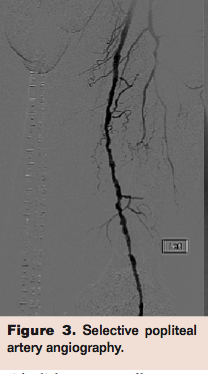

CLI patients tend to have severely calcified arteries, posing a challenge to both surgical and endovascular revascularization techniques. Surgical bypass is feasible in ambulatory patients with a reasonable surgical risk, long occlusions, a patent IP artery that provides direct flow to the foot, and an adequate autologous venous conduit. The candidacy of CLI patients for bypass is often compromised by poor or inadequate length of autologous vein, poor skin nutrition, significant medical comorbidities and calcified, diseased targets. From the endovascular standpoint, one of the most common challenges is the severely calcified lesion that is not dilatable by balloon angioplasty, leading to an unresolved high-grade stenosis (Figures 1-3). These resistant, recalcitrant lesions are also associated with spiral dissections and perforations and can present a physical barrier for the penetration of the antiproliferative drugs delivered by current drug-eluting stents and balloons. They have also been recognized as one of the predisposing factors that lead (in conjunction with forces of contraction, extension, torsion, compression, and flexion) to stent fractures (Figure 4).